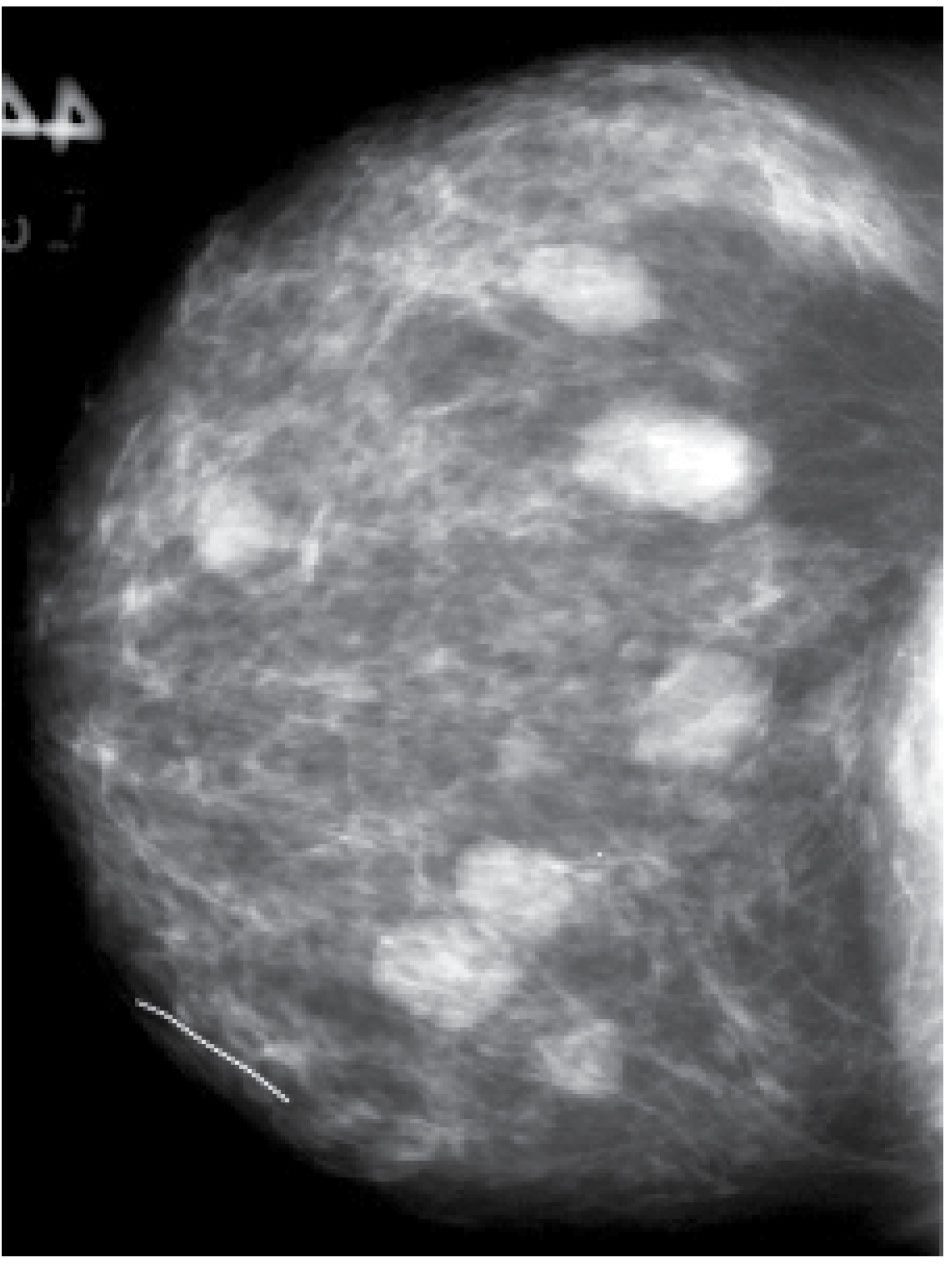

Mammographic and Ultrasound Analysis of Breast Masses Radiology Key

Mammographic and Ultrasound Analysis of Breast Masses Radiology Key What Does A Mass Mean In The Breast Breast cysts tend to affect. The cancer cells might form a mass called a tumor. A breast lump is a mass, growth, or swelling within the breast tissue. A breast lump is a mass or growth that develops in your breast. They will also feel as though they are attached to. A breast lump is a growth of tissue that. What Does A Mass Mean In The Breast.

Mammographic and Ultrasound Analysis of Breast Masses Radiology Key What Does A Mass Mean In The Breast A breast lump is a mass or growth that develops in your breast. A breast lump is a mass, growth, or swelling within the breast tissue. A breast lump is a growth of tissue that forms in the breast. A breast mass has volume and it occupies space. Breast cysts tend to affect. Cancerous lumps tend to feel firm, almost. What Does A Mass Mean In The Breast.